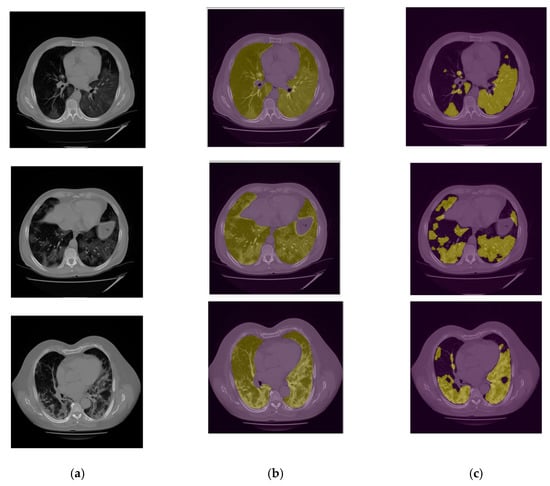

2.3. Image Segmentation Models and Output

2.3.1. Lung Segmentation

2.3.2. Infection Area Segmentation

2.3.3. Segmentation of GGO and Consolidation Patches